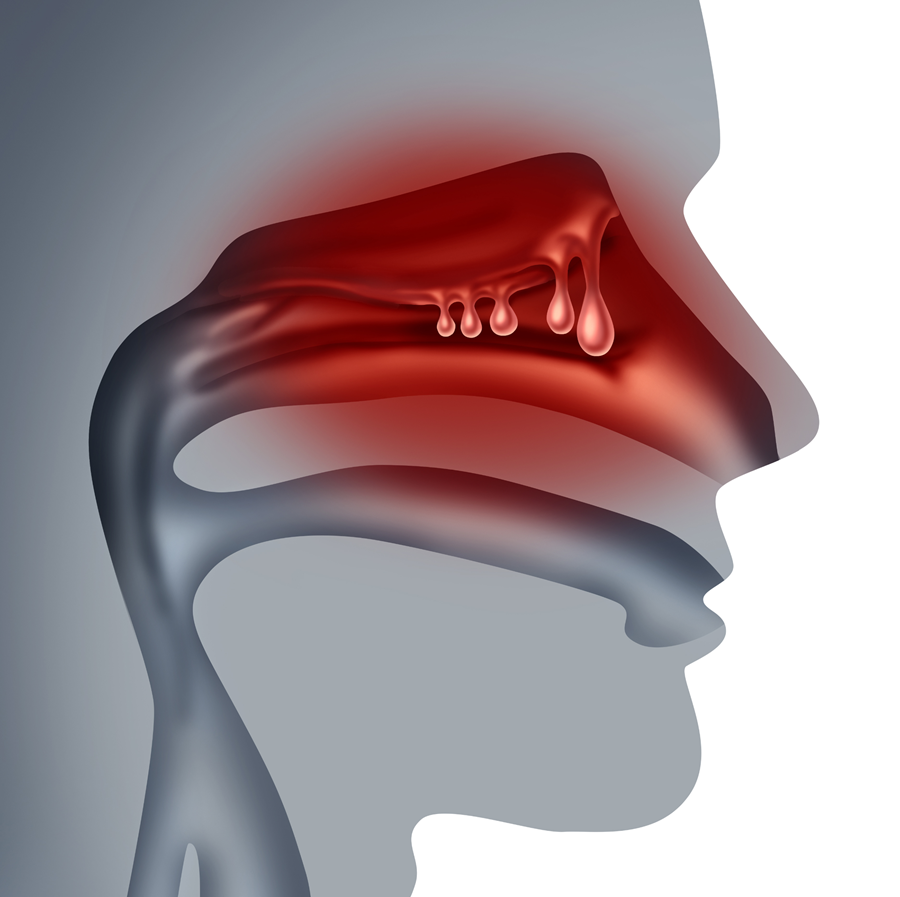

Traitements biologiques et rhinosinusite sévère avec polypes nasaux : étude belge en vie réelle

Parmi 167 patients atteints de CRSwNP, 144 ont reçu du mépolizumab et 23 de l’omalizumab. Après 24 semaines, les deux traitements ont nettement amélioré les résultats rapportés et le NPS, avec des effets significatifs dès 12 semaines, et une réduction supplémentaire du NPS sous mépolizumab.